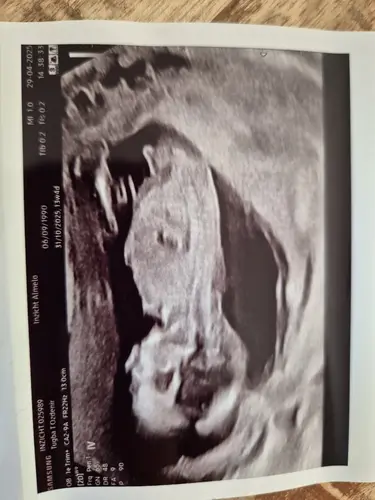

I think its a girl.

Could you olease evaluate the other two pictures below?馃槆

In the 3rd picture it looks

Like a boy. The other 2 girls